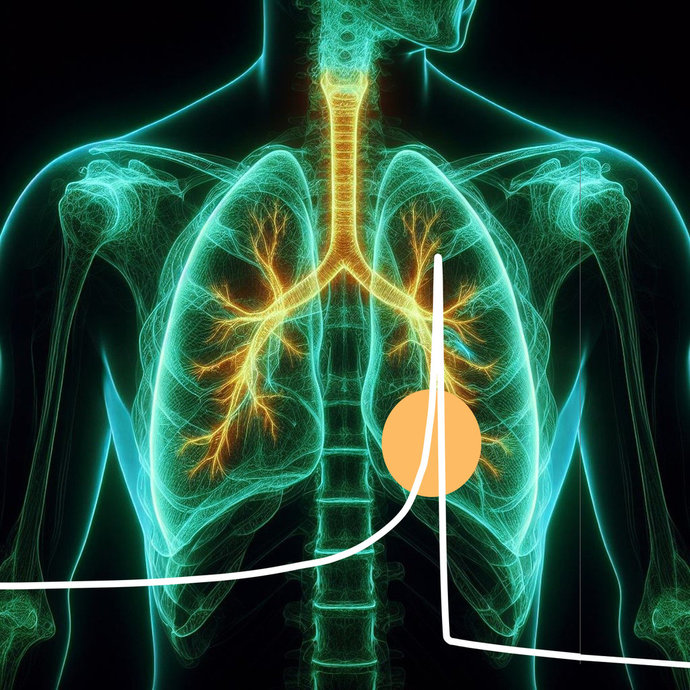

Biophysics & Tumor Therapy with Ion Beams